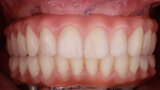

Fig. 16. Rx Pre-operatoria, Prótesis híbrida inmediata con 6 años de evolución y Rx Control a los 6 años.

Fig. 17. Rx Pre-operatoria, Prótesis híbrida inmediata con 6 años de evolución y Rx Control a los 6 años.

Fig. 18. Rx Pre-operatoria, Prótesis híbrida inmediata con 6 años de evolución y Rx Control a los 6 años.